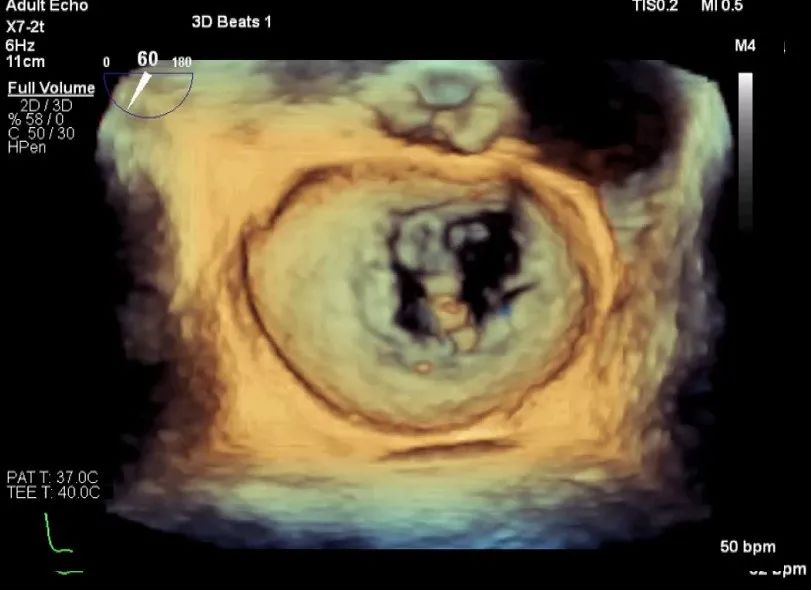

3D视图打开夹子

X-plane:下第夹子尝试捕获2区

X-plane:测量前叶长25mm,后叶长14.2mm

X-plane:计算前叶捕获长度8mm,后叶捕获长度7mm

3D视图下观察二尖瓣双孔形态

3D-color:残余少量返流